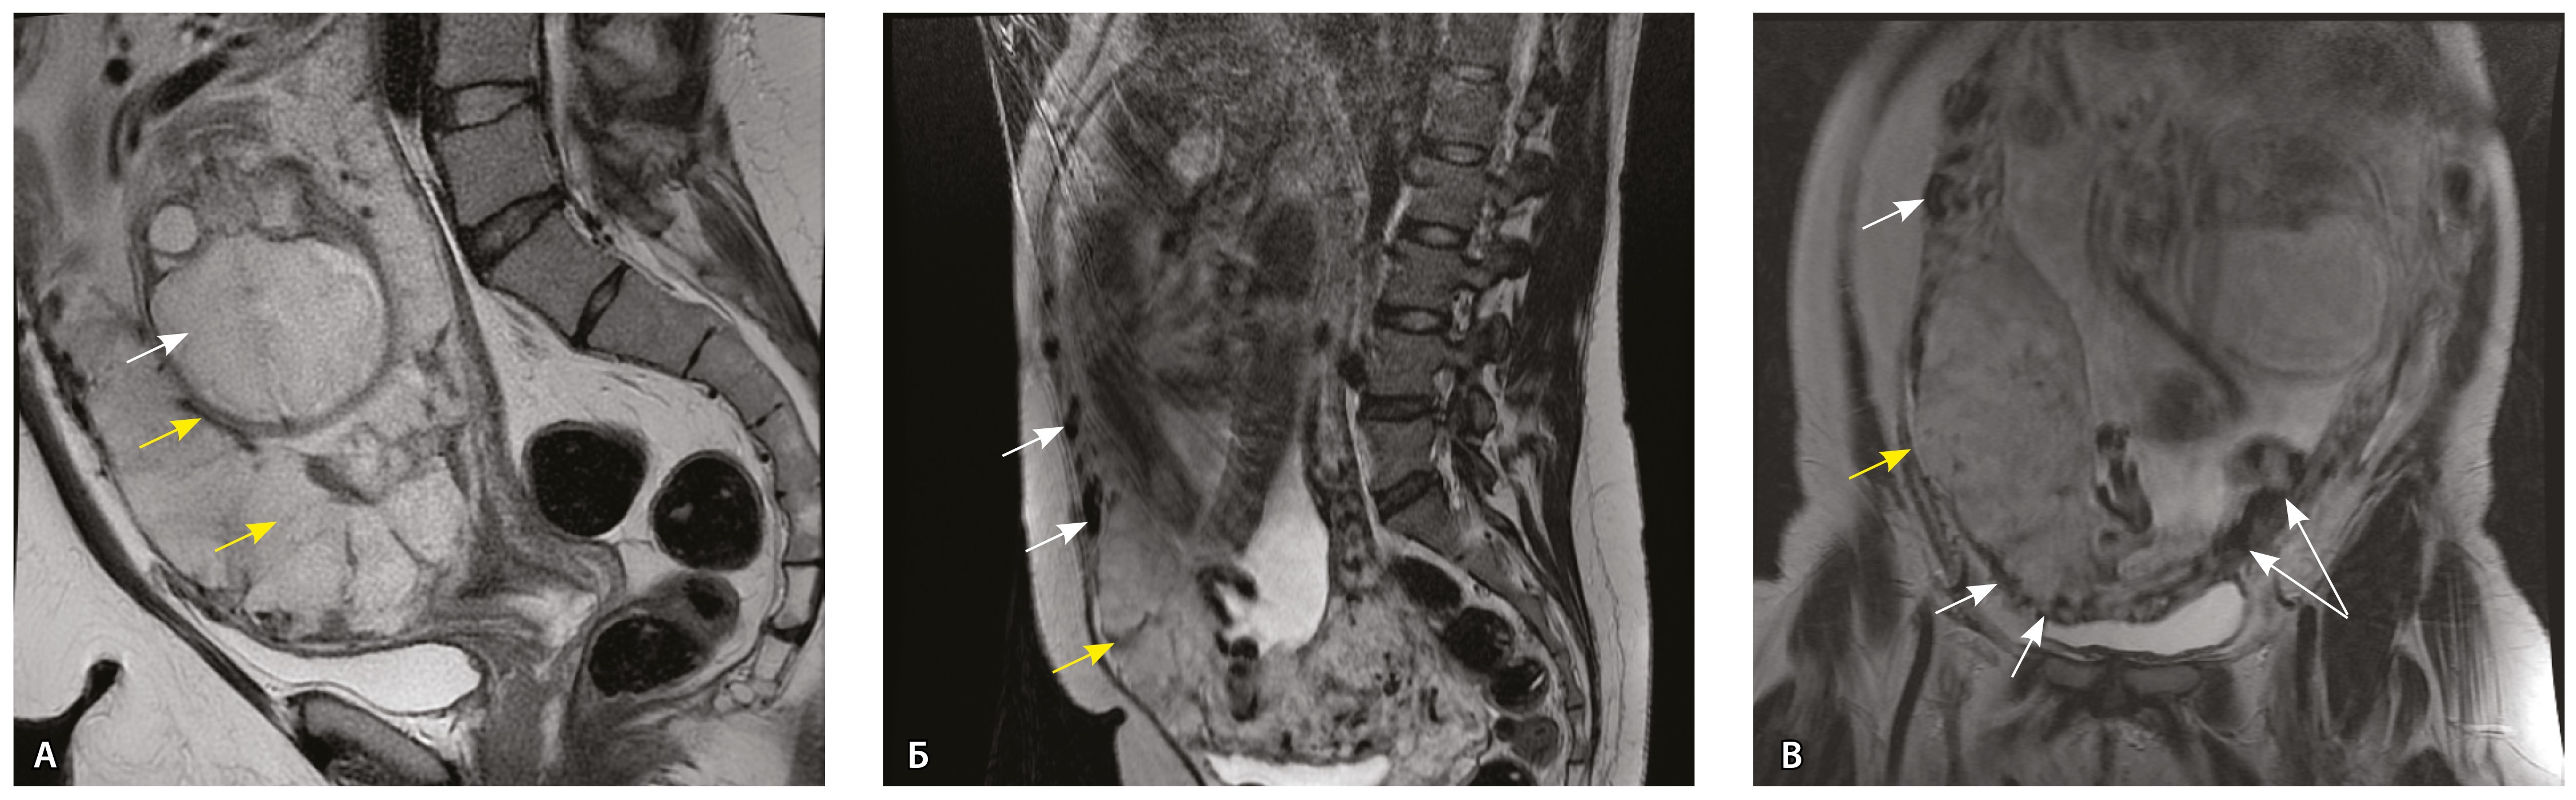

На микропрепаратах васкуляризация серозной оболочки представлена множеством крупных сосудов, идущих в разных направлениях и анастомозирующих друг с другом. Возможно, имеются артериовенозные соустья. На серийных срезах также видно, что в стенках артерий трудно различимы два слоя миоцитов (продольный и поперечный). Со стороны адвентиции они окружены толстым «футляром» из грубоволокнистой голубой ткани (при окраске по Маллори). Она проникает в стенку артерий, замещая мышечный слой (рис. 12).

Рис. 12. Истончение миометрия; в составе серозной оболочки видна крупная артерия, окруженная плотной соединительной тканью. А – cосуды в составе серозной оболочки (окраска по Маллори; × 200), не дифференцированная на мышечные оболочки стенка артерии, справа – вена, оба сосуда покрыты фиброзной оболочкой, внизу виден слой мезотелия в составе серозной оболочки; Б – серийный срез тех же сосудов при окраске на выявление эластических волокон, сосуд с соединительнотканной муфтой (окраска по Вейгерту; × 50): определяется полная дезорганизация эластичного материала в стенке; стрелкой указан мезотелий (аналог pl. increta, PAS 2 по FIGO)

Эластический каркас представлен сетью тонких волокон, без концентрации на внутреннюю и внешнюю мембраны. Однако маркер СD34 констатирует сохранение эндотелия, что свидетельствует о том, что по артериям циркулирует кровь, не сворачиваясь (рис. 13).

Рис. 13. Самые крупные сосуды в пределах серозной оболочки стенки матки: А, Б – серийные срезы артерии; × 50. При окраске по Маллори (А) видна тонкая полоска мезотелия (черная стрелка), слабо дифференцированная мышечная стенка артерии, вокруг нее – плотная коллагеновая оболочка (желтая стрелка), в просвете определяются тромботические массы. При окраске по Вейгерту (Б) наблюдается полная потеря внутренней и внешней эластических мембран

Сосуды 5-го типа. Наличие гиперваскуляризации за пределами матки по данным МРТ, на границе с мочевым пузырем с вовлечением его стенки, сосуды в области перешейка матки, параметрия, в том числе в сочетании с признаками фиброза, наличием рубцово-спаечных изменений и др. Можно предположить, что сосуды 5-го типа являются аналогом pl. рercreta PAS 3b, 3c (рис. 15).

Рис. 15. Беременность 34 недели, pl. percreta, PAS 3b по FIGO (A, Б), PAS 3c по FIGO (В). На магнитно-резонансных томограммах в режиме Т2-взвешенного изображения в сагиттальной (A, В) и аксиальной (Б) плоскостях определяется гиперваскуляризация в области выраженно истонченного нижнего маточного сегмента с распространением сосудов на заднюю стенку мочевого пузыря в области дна (белые стрелки), в область перешейка матки (желтые стрелки)

Данный вариант в патоморфологической картине наиболее сложен для оценки ввиду того, что такие структуры, как параметрий, перешеек матки, стенка мочевого пузыря, обычно не предоставляются в виде макропрепаратов, поэтому визуальные методы, в частности МРТ, могут с большей точностью оценить вовлеченность смежных структур. На микропрепаратах данный вариант инвазии плаценты сочетается с рубцово-спаечными изменениями задней стенки мочевого пузыря с нижним маточным сегментом (рис. 16).